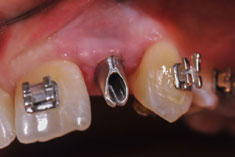

Die Nichtanlage der seitlichen oberen Schneidezähne und der zweiten unteren kleinen Backenzähne (Prämolaren) ist relativ häufig.

Wir verfügen über eine jahrzehntelange Erfahrung in der kieferorthopädischen Vorbehandlung, Implantologie und der prothetischen Versorgung von Nichtanlagen, sowie der Chirurgie und der Einordnung von verlagerten bleibenden Zähnen ohne den Einsatz von Implantaten.